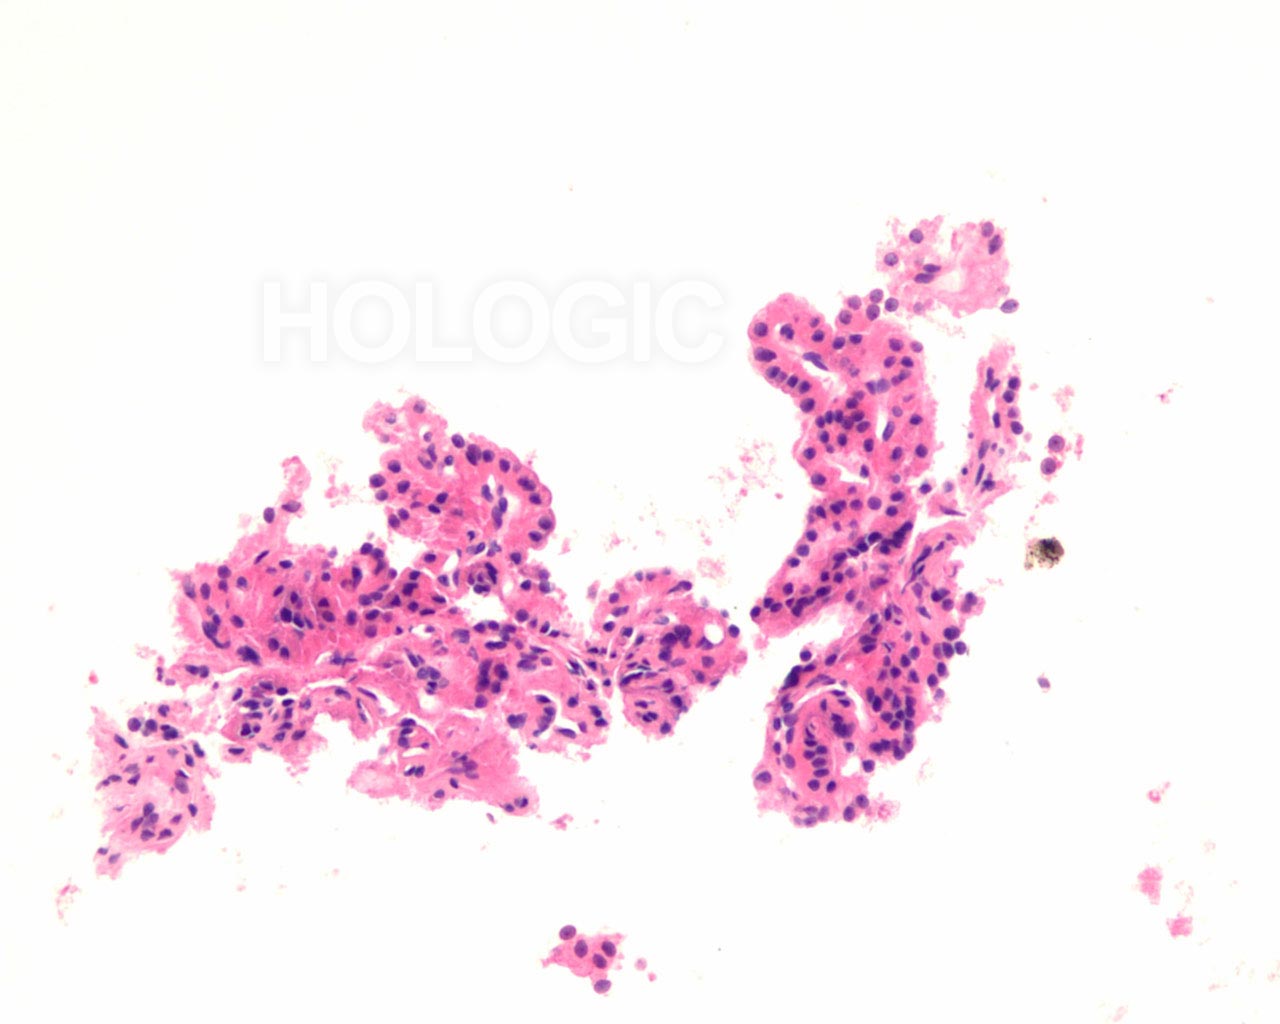

Met celblokken kan de afmeting van de follikel beoordeeld worden op een manier die een aanvulling vormt op de ThinPrep-glaasjes. Om een follikel als groot aan te merken, moeten de folliculaire cellen over een tamelijke grote afstand 2-dimensionaal georganiseerd zijn; als de follikels klein zijn, bevinden de cellen zich niet in een brede 2-dimensionale, platte laag. Het is verrassend moeilijk het eens te worden over de definitie van ‘macrofolliculair’ [9]. Acht tot 10 folliculaire celdiameters lijkt een redelijke definitie voor de macrofolliculaire colloïd fragmenten [9], of voor de diameter van platte, 2-dimensionele macrofolliculaire lagen. In weefselcoupes die loodrecht op een macrofolliculaire groep zijn gesneden, zien de macrofollikels eruit als een lineaire ordening van ten minste 8 folliculaire cellen. Als de sectie in het vlak van een macrofolliculaire groep snijdt, kan men gemakkelijk een solide uitziende celmassa tegenkomen die analoog is aan een weefselcoupe die tangentieel recht door de ductale cellaag snijdt in een schildklier biopsie. Net als pathologen een dergelijke tangentiële coupe kunnen herkennen en kunnen onderscheiden van ductale hyperplasie, kan men een tangentiële coupe door macrofolliculaire groepen herkennen. Dit wordt hieronder geïllustreerd. Microfollikels hebben per definitie een hoge ratio tussen de cellen en het colloïd en de cellen kunnen niet in een brede 2-dimensionele laag liggen. In celblokcoupes vertonen microfollikels geen lange lineaire organisatie van cellen. Renshaw et al. vonden een significante grijze zone onder experts in het onderscheid tussen microfolliculaire en macrofolliculaire groeperingen op cytologische preparaten [9].Een van de belangrijkste grijze gebieden betreft het probleem van folliculaire cellen die artefactueel op elkaar zijn gestapeld. Deze artefactuele stapeling van cellen lijkt gemakkelijker te diagnosticeren in weefselcoupes. Een ander probleemgebied betreft die gevallen waarin microfollikels en macrofollikels door elkaar zijn gemengd. Het is ons en anderen opgevallen dat benigne stromanodulen vaak plat cytoplasma vertonen in de cellen van de microfollikels. De robuustere cellen van een folliculair neoplasma tonen vaak veelal kubusvormige of zelfs cilindrische, folliculaire cellen die de microfollikels bekleden [7]. Deze kenmerken zijn duidelijk in celblokcoupes en worden hieronder geïllustreerd.

Benigne folliculaire nodulen vertonen vaak een bijmenging van cytologisch verschillende typen folliculaire cellen. De follikels van folliculaire neoplasmen zijn meestal uniform van aard. Hoewel het uiterlijk van de follikels in een cytologisch preparaat van groep tot groep kan worden vergeleken, kan deze benadering van het beoordelen van de klonaliteit soms moeilijk zijn. Het kan bijvoorbeeld onmogelijk zijn om te weten of de FNA-naald buiten het neoplasma monsters heeft genomen. Met celblokken kunnen de morfologische kenmerken van waarlijk aangrenzende follikels over een bereik van enkele honderden microns geëvalueerd worden, zoals hieronder geïllustreerd wordt.

Er zijn enkele verschillen in het uiterlijk tussen kernen in directe uitstrijken, ThinPrep® en celblokken. Een voordeel van celblokken is dat ze een gemeenschappelijk platform vormen dat kan worden gedeeld met chirurgische pathologen die de uiteindelijke diagnose stellen op basis van een biopsiemonster. We illustreren het nut van deze benadering voor de classificatie van FNA’s van problematische laesies met folliculair patroon met gedeeltelijk ontwikkelde nucleaire kenmerken van papillair schildkliercarcinoom [3].

Folliculaire neoplasmen tonen in tegenstelling tot een papillair schildkliercarcinoom compacte aggregaten van heterochromatine. Het is onze ervaring dat de kern van een papillair carcinoom grofweg kan worden onderscheiden van kernen van folliculaire carcinomen, doordat papillaire schildkliercarcinomen vaak meer lineaire aggregaten chromatine vertonen (erg oppervlakkige vouwen van de nucleaire envelop) dan ronde of geklonterde chromatinemassa’s. Deze kenmerken worden hieronder geïllustreerd.